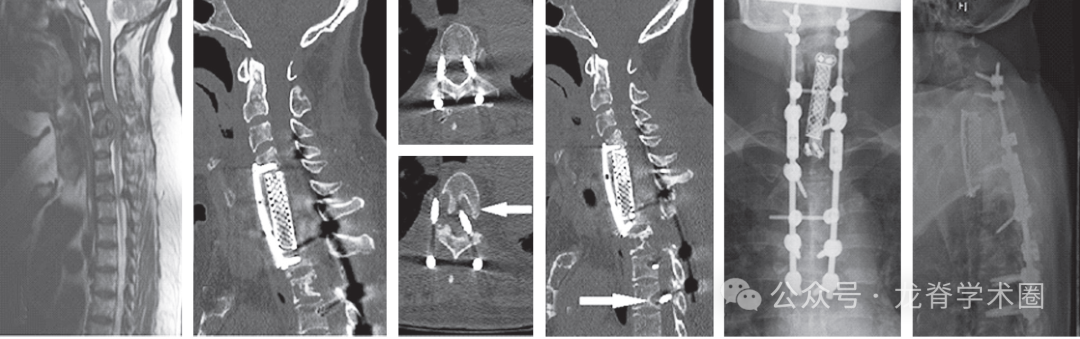

2005年至2015年共有288例患者接受了MSTS。42例患者被排除在外,因为他们在手术后30天内死亡,或者他们的MSTS没有使用内固定。因此,最终包括246例患者。5.7%(14/246)的受试者出现SF,其中71%(10/14)的患者进行了翻修手术。所有的SF都是Construct failure,然而,没有SF是绝对意义的Implant failure。16%(41/246)的患者在研究结束时表现出无临床症状的Implant failure/Construct failure的影像学证据。

患者平均年龄58.8岁,127名男性(51.6%)和119名女性(48.4%)。常见的肿瘤类型为肺癌(27.6%)、乳腺癌(16.7%)、血液系统肿瘤(12.9%)、肝癌/胃癌/肠癌(10.9%)、肾癌(9.3%)、前列腺癌(8.9%)。大多数(66.3%)病变为溶骨性病变。中位生存期为13.4个月。SF患者的中位生存期为21个月。从手术到SF的平均为12.8±17.7个月,到内固定失败的中位时间为5个月。SF患者中,顽固性疼占78.5%(11/14);新发神经功能障碍占50%(7/14);假体移位占14.2%(2/14);继发性伤口裂开占7.1%(1/14)。64.3%为SINS评分7-12分, 35.7%)为SINS评分>12分。13/14(92.8%)的内固定跨越交界区。49例(19.9%)采用MIS手术,194例(78.9%)采用开放手术。对SF患者手术类型进行亚组分析,4例(28.6%)患者行MIS, 10例(71.4%)患者行开放手术。手术类型与SF无明显相关性。

单因素和多因素竞争风险回归模型显示,术前活动状态(ECOG≤2)是SF的重要危险因素,死亡是一个竞争事件。术前SF患者11例(78.5%)可以走动,3例(21.4%)不能走动。使用助步器的患者发生种SF的风险高出7倍。此外,由于所有SF患者SINS>7分,因此SINS>7分是一个危险因素。同样,SINS>12分也具有显著性。两组间的亚组分析显示,SINS评分>12的SF发生率为11.9%(5/42),高于SINS评分为7-12分,5%(9/178)。这一差异具有统计学意义。跨越交界区是另一个危险因素,93%(13/14)的SF患者跨越交界区。

结论:MSTS患者SF的发生率较低(5.7%)。术前使用助步器患者的SF风险比不使用助步器的高7倍。术前SINS>7分和内固定跨越交界区与SF相关。大多数内固定失败发生在假体-骨界面。